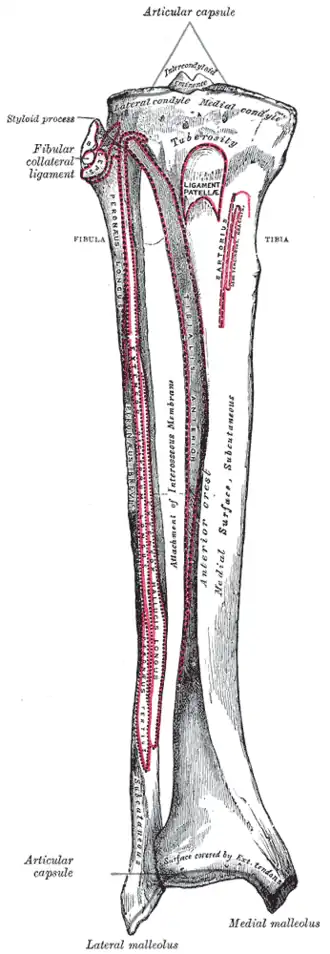

Bones of the right leg. Anterior surface.

Bones of the right leg. Anterior surface. -

The tuberosity of the tibia gives attachment to the patellar ligament, which attaches to the patella from where the suprapatellar ligament forms the distal tendon of the quadriceps femoris muscles. The quadriceps muscles consist of the rectus femoris, vastus lateralis, vastus medialis, and vastus intermedius. These quadriceps muscles are innervated by the femoral nerve.[1] The tibial tuberosity thus forms the terminal part of the large structure that acts as a lever to extend the knee-joint and prevents the knee from collapsing when the foot strikes the ground.[1] The two ligaments, the patella, and the tibial tuberosity are all superficial, easily palpable structures.[2]